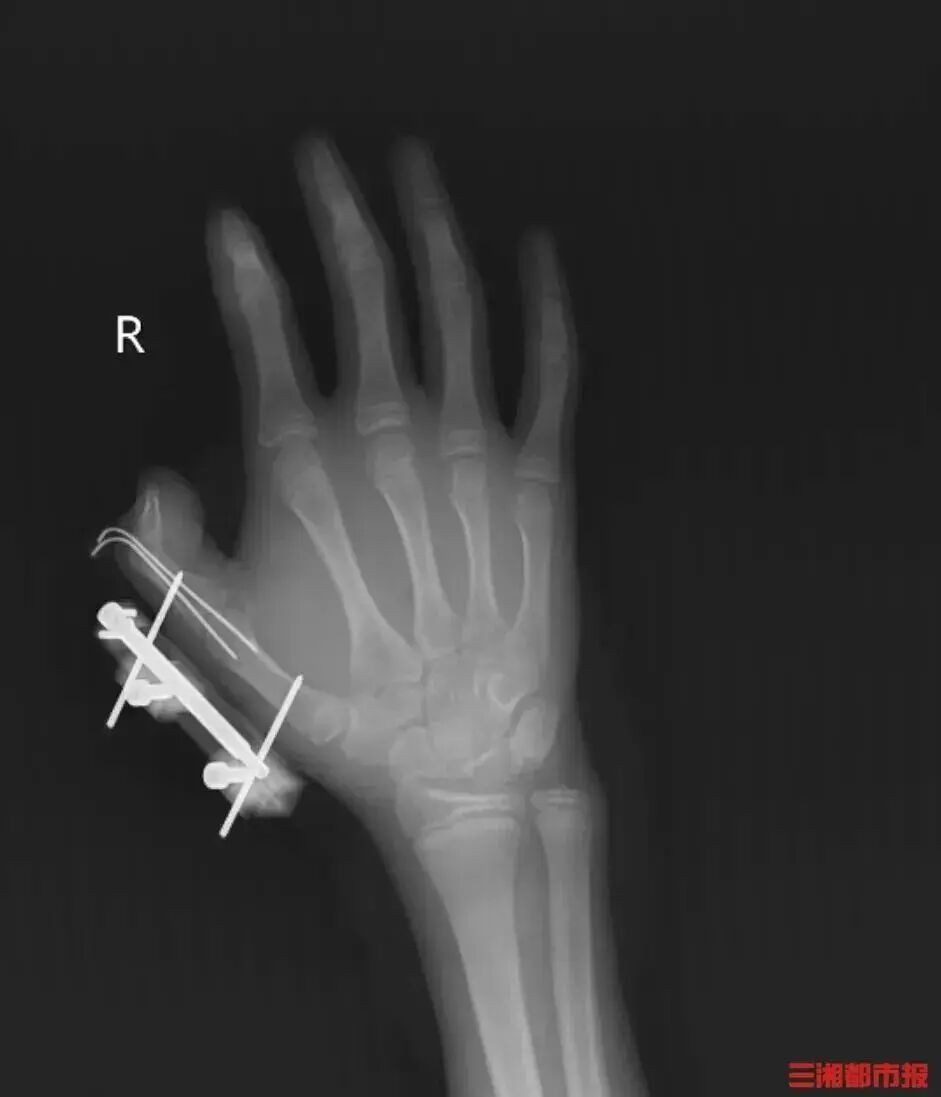

冰镇冷饮冰激凌 为冷链食物保鲜 制作“仙气飘飘”的网红饮料 …… 干冰在日常生活中十分常见 但很多人不知道 干冰若储存、使用不当 便会“暗藏杀机” 把干冰当玩具摇 14岁少年手指被炸得深可见骨 前不久,湖南一名14岁的少年维维(化名),在爸爸网购冰激凌的箱子里发现了用于冷藏的干冰,便拿走当成玩具玩,捏在手里反复摇晃。 突然,密封袋里的干冰发生爆炸,维维的右手瞬间鲜血直流,拇指虎口处被撕开一道约10厘米的伤口,深可见骨,肌肉组织断裂外露,还伴随着拇指骨折、关节脱位,整个拇指完全失去知觉。 见状,家人赶紧带他到当地医院包扎,随后紧急转往湖南省人民医院手足显微外科。经治疗,维维的拇指保住了,但后续还需长期康复训练,才能慢慢恢复手部精细动作功能。 维维懊悔不已:“早知道干冰这么危险,我绝对不会去玩。” 干冰不是“冰” 爆炸威力堪比鞭炮 干冰,又名固态二氧化碳,通常为无毒无味的白色固体,形状不一。干冰在常温常压下,可以直接升华成二氧化碳气体,升华时体积膨胀800倍至1000倍,加入热水后会急剧加速升华产生大量烟气。 湖南省人民医院手足显微外科主任陈建民介绍,如果将干冰装在密封袋里摇晃,随着气体不断增多,袋子承受不住压力就会爆炸,爆炸产生的威力是普通鞭炮的数倍,瞬间的杀伤力不容小觑。 干冰使用不当 可能造成致命危险 爆炸 在密闭容器中使用干冰:干冰在常温下易转化为二氧化碳气体,导致密闭容器内压力升高,超过容器承受极限后产生爆炸。 ▲图源:广东消防 在冰箱内放置干冰:干冰的升华温度约为-78.5℃,而冰箱冷冻室的温度在-4℃至-24℃之间,因此干冰放入冰箱后,会持续升华产生大量二氧化碳气体,致使冰箱内部压力过大,发生爆炸。 ▲图源:广东消防 窒息 干冰升华后产生的二氧化碳气体会导致人呼吸困难,如果在较封闭的空间内,短时间就可引发窒息,危及生命。 冻伤 干冰是温度在-78.5℃以下的固态二氧化碳,直接接触皮肤会瞬间带走热量,非常容易造成冻伤,甚至导致皮肤坏死,重则伤及肌肉、骨骼。 收到冷链包裹 如何安全处理干冰? 别让孩子触碰 家长要把干冰放在孩子拿不到的地方,防止儿童因为其“烟雾缭绕”而好奇把玩,明确告诉孩子干冰不是玩具。 拒绝密闭空间 切勿将干冰存放在矿泉水瓶等密闭容器中,或保存在冰箱里;干冰要放置在通风良好的地方。 不要在汽车等密闭空间内存放使用干冰。 接触必戴防护 不要直接接触干冰,为避免冻伤,可使用防冻手套或夹子拿取干冰。 受伤立即就医 当人体皮肤接触干冰后出现冻伤,应对周围皮肤热敷并使用冻疮膏进行处理,若冻伤情况严重,应及时就医。 一旦被干冰炸伤,应马上就医,以免耽误治疗。 干冰是生鲜冷冻“保鲜利器” 在此提醒 收到干冰应通风放置妥善处理 密封存放会爆炸 徒手接触易冻伤 若不慎被干冰炸伤冻伤 请立即就医